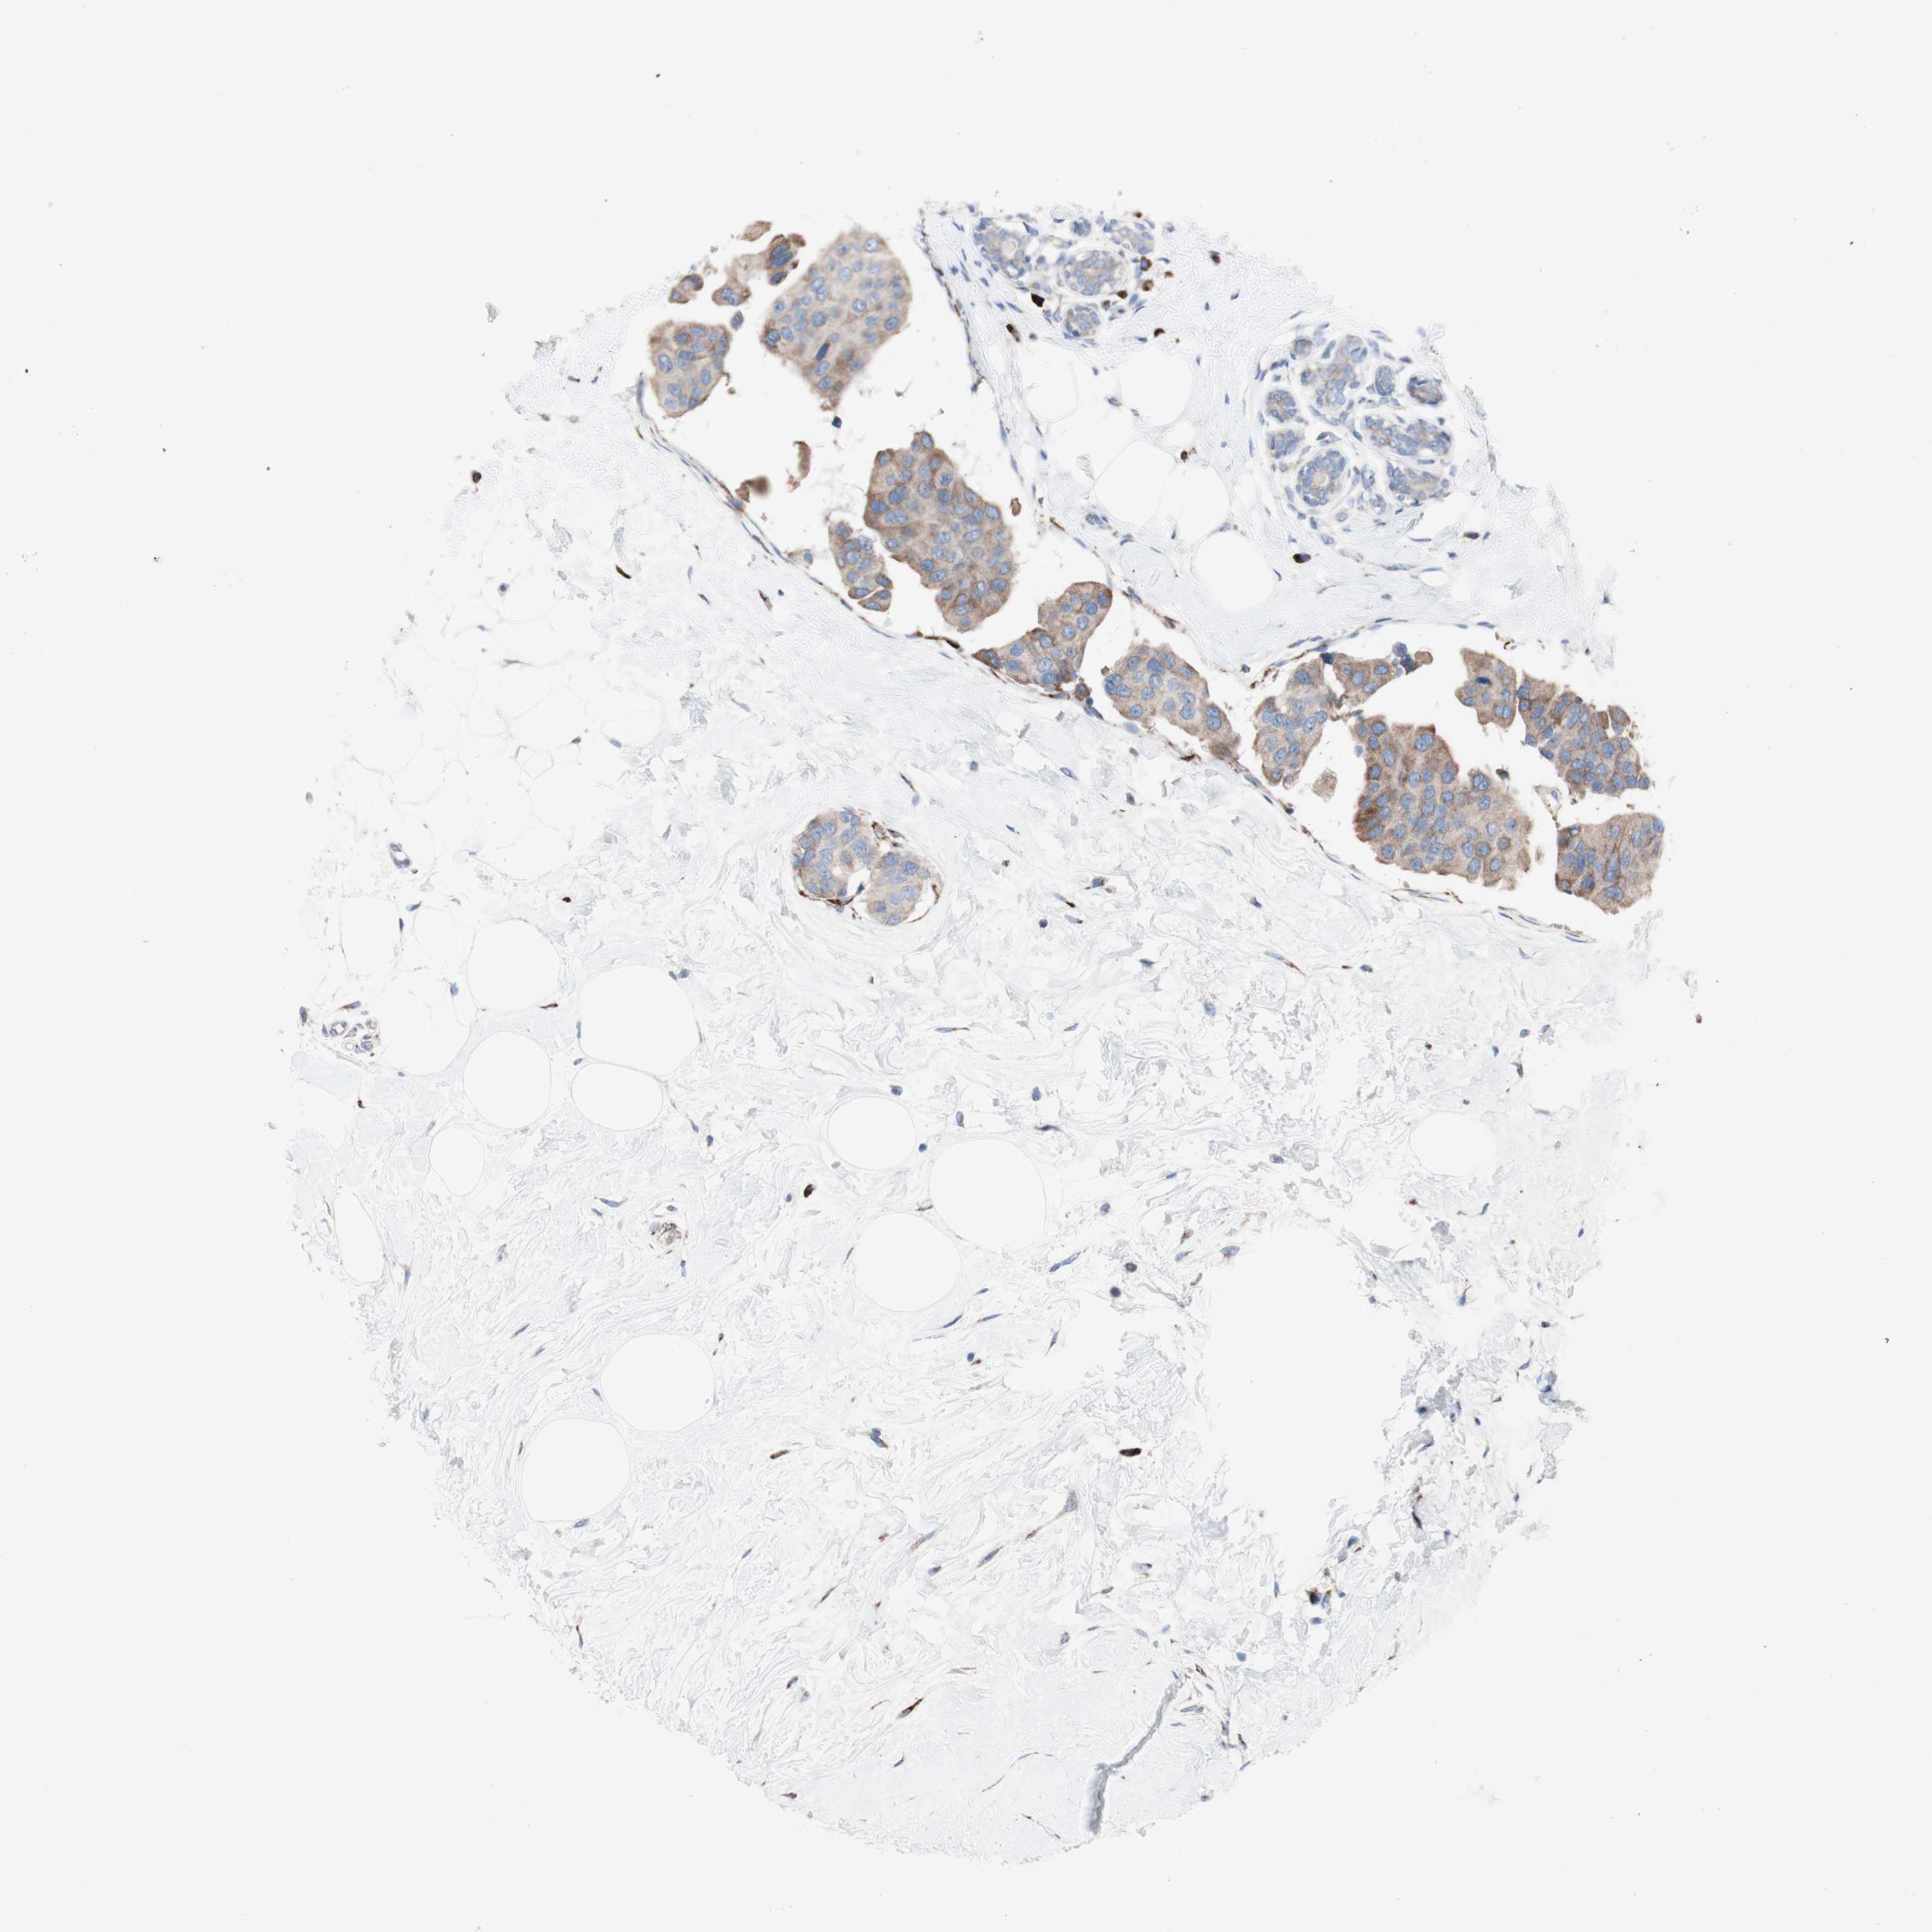

BRCA TCGA BRCA VALIDATION PROTEIN EXPRESSION

ANTIBODIES

AND

VALIDATION